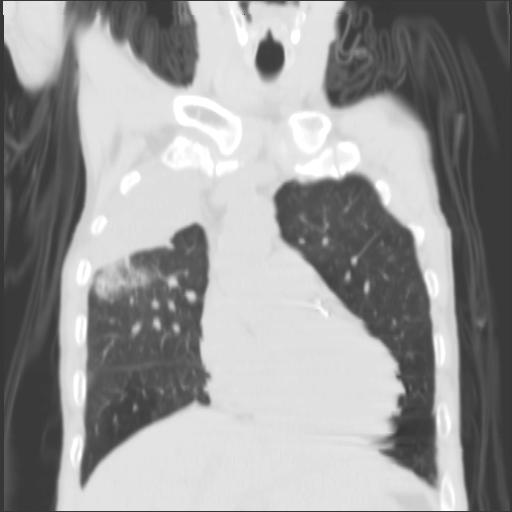

CT52348:男,63岁,反复咳嗽、咳痰2月余,请会诊。多谢!

本帖最后由 cefcmj 于 2016-11-7 20:52 编辑 男,63岁,反复咳嗽、咳痰2月余,请会诊。多谢!

右肺上叶可见大块大片及斑片状影,右上支气管开口闭塞。纵膈内可见肿大淋巴结。考虑:右肺上叶中央型肺癌伴阻塞性炎症、阻塞性不张。纵隔淋巴结转移。

右上中央型肺癌,肺不张。

右上中央型肺癌,肺不张、肺炎,建议增强扫描。

右上中央型肺癌